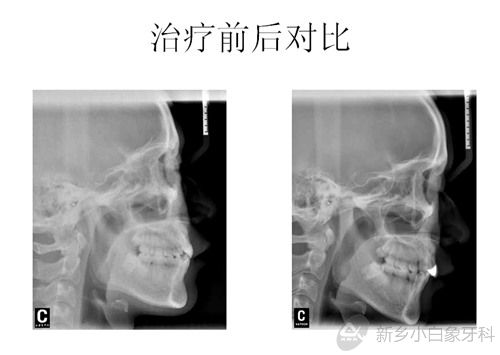

治疗计划:全口固定矫治术;拔除14.24.35.45;排齐与整平牙弓;关闭拔牙间隙;调整咬合关系;11.21根尖处多生牙择期拔除;全口洁治。

于2014年12月12日治疗结束,患者非常满意。